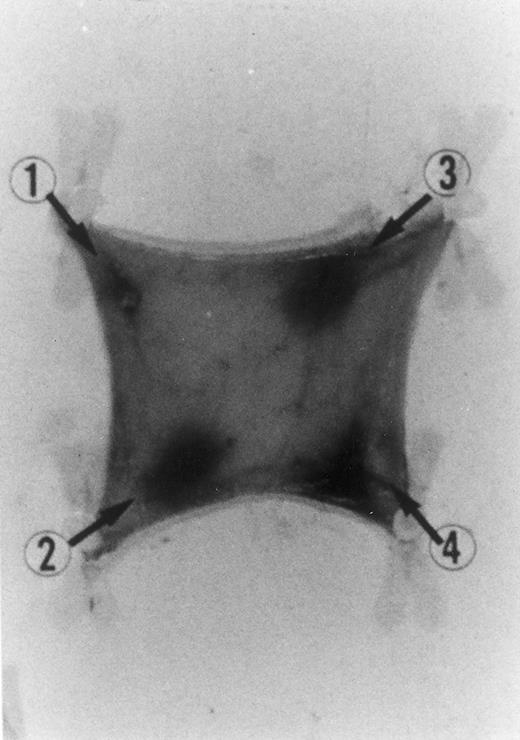

Evan's blue-stained intradermal injection sites showing the kinetics of the dermal response to exogenous human RANTES 10 ng/50 μL (c) and MCP-1 10 ng/50 μL (d); while (a) is a negative control (PBS 50 μL) and (b) is a positive control (FMLP 10−6 mol/L in 50 μL). This representative experiment was found to be reproducible and has been performed at least three times.

Intradermal injection sites of chemokines RANTES and MCP-1.In order to assess the inflammatory activities of RANTES and MCP-1 in an in vivo model we have injected 50 μL of these chemokines in four distinct sites of the abdomen of rats for the duration of 4 hours. At this time point animals were killed in accordance with previous data indicating that 4 hours is the optimal time for chemokine-induced chemoattraction.23-26 RANTES and MCP-1 were used at 10 ng/50 μL; while the chemoattractant peptide FMLP was used at 10−6 mol/L.8 In Fig 1 PBS (a, negative control) was not effective in promoting inflammation; RANTES at 10 ng/50 μL (c) enhanced dye extravasation at a greater extent than FMLP 10−6 mol/L (b, positive control); while MCP-1 at 10 ng/50 μL (d) was less effective than FMLP. In Table 1 we report a representative experiment with 12 treated rats. After chemokine challenge (4 hours) we calculated the mean ± S.D. of the major diameters (in mm) of dye extravasation at the site of injections (4 rats). Reported P values were obtained by comparing the effect of RANTES to MCP-1.